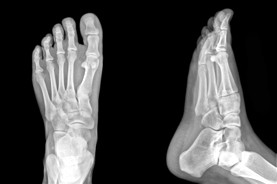

At the Calgary Foot Institute, our Doctors are trained to specifically treat problems associated with your feet or ankles. Below are several of the most common problems that we see on a day to day basis: